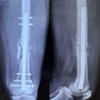

A radiological assessment with anteroposterior and lateral X-rays was done. The fracture was classified using the AO/OTA or Muller classification [3]. The patients were operated using the standard Swashbuckler approach [3,4]. Proper post-operative rehabilitation played a major role in the recovery of the range of movement and improved the power of the quadriceps and the functions of the joint. Rehabilitation was customized according to the patient and the fracture type. Patients were followed up at 1st, 2nd, 4th, 6th month, and 1-year intervals. The results were clinic radiologically assessed with anteroposterior and lateral radiographs at each follow-up. The fracture was said to be radiologically united if the callus was seen in at least three cortices in anteroposterior and lateral views. The functional outcomes were analyzed using the Neers knee scoring system.

Union was found in 47 patients with two patients presenting with non-union. Among the 47 patients, seven patients presented with malunion. Two patients who presented with non-union required reoperation. The average union time of the fracture was 12–20 weeks with the mean time of union being 16.2 weeks. All patients were successfully given a walking aid by the 20th week.

Twenty-eight out of 49 patients developed complications (57.14%). Eleven developed knee stiffness, three developed surgical site infections, and three developed both. Limb length discrepancy was found in two patients, varus angulation and malunion were found in seven patients, and non-union was found in two patients. Reoperation is required in two cases due to non-union. The knee score value was not significant with respect to age, sex, mode of injury, type of fracture, associated injury, and AO type. Of the 36 C2 strains, 15 had excellent results, 13 had good results, six had fair results, and two had poor results. Only one patient with type C3 was included and the results were negative.

Surgical stabilization at an early stage can facilitate care of the soft tissue, it permits early mobility and reduces the complexity of nursing care. Open reduction and internal fixation have been the treatment of choice. A variety of implants used were angled blade plates, dynamic condylar screws (DCS), condylar buttress plates and interlocking nails, and LCP. A certain amount of good bone stock is required to fix angle devices such as condylar blade plate along with DCS to insert the lag screw and its entry makes a significant amount of bone loss from the lag screw entry site which itself compromises already fractured condyles; hence, it limits their use in some fracture type of intra-articular fracture. This was solved by condylar buttress plates for comminuted fractures. However, with standard buttress plating, these fractures often fall into varus deformity. The failure rate was high especially in osteoporotic bone. In 1973, Connoly advocated closed reduction and cast brace ambulation while in 1974, Schatzker[5] reported superior results using operative methods. Also in 1967, Neer[6,7] classified supracondylar/ intercondylar fractures, used straight plate and screws and considered conservative treatment was superior to internal fixation. Zehntner mk et al(1992) [8] evaluated 59 supracondylar & intercondylar fractures in 57 patients after a mean follow up of 5 years and 7 months after internal fixation using AO/ASIF technique. Axial alignment was compared with that of the uninjured side. Differences were within 5 degrees for more than 75% cases. Alignment differences were more frequent in complicated and intercondylar fractures. Simonian et.al (1998) [9] described push screw and double plating for fixation of distal femoral fractures as these fractures have a unique problem of loss of fixation of distal fragment. Loss of distal fixation leads to toggling distal screws which can lead to varus angulation and fracture fixation failure. Less Invasive Stabilisation system has been developed to provide multiple fixed angle distal locked screws and can be best thought as a submuscular internal fixation[9]. Biomechanical studies revealed that gross loosening of the standard condylar buttress plate and DCS occurred due to the toggle at the screw-plate interface, which leads to early implant loosening resulting in breakage of the implant and varus/valgus collapse of the distal fragment. To address these issues, a first-generation locking condylar plate was designed. Screw-plate toggle and motion at the bone-screw interface are minimized by a locking plate and provide more rigid fixation. Rigid fixation is felt to be one key to the successful treatment of these fractures. The conventional plates are associated with their own demerits such as screw pullout, implant failure, and unstable fixation needing post-operative immobilization. Delayed post-operative mobilization results in stiffness of the knee which is an indicator of poor outcome. The invention of a locking condylar buttress plate made fixation in osteoporotic and comminuted fractures easier. Hence, now with the evolution of locking compression plating for distal femoral fractures, especially for the comminuted intra-articular fractures, many of the older demerits could be addressed which includes the increased stability due to locking compression plating principle, multiple screw options in the distal fragment providing option for fixing the multiple fragments restoring the anatomical congruity and providing stable fixation of the distal fragment with the proximal fragment with resulting increased stability allowing for early mobilization. Current fracture patterns that we encounter are complex comminuted types due to the prevalence of high-speed vehicles mainly due to the high two-wheeler population in countries such as India. Improved health-care results in a longer life span and subsequently presents us with more osteoporotic fractures which were previously treated using conservative methods. The LCP is a single-beam construct where the strength of its fixation is equal to the sum of all screw-bone interfaces rather than a single screw’s axial stiffness and pullout resistance in unlocked plates. Its unique biomechanical function is based on splinting rather than compression resulting in flexible stabilization, avoidance of stress shielding, and induction of callus formation. It can also be used as biological fixation without disturbing the fracture site. Another fixation method is a less invasive stabilization system. The main difference between the distal femur-LCP and the LISS is that the LISS utilizes an outer jig device for shaft holes, functioning essentially as a locking guide jig, which is attached to the distal part of the plate and guides the placement of the proximal locking screws. The shaft holes on the distal femur-LCP are oval allowing for the options of a compression screw or a locking screw. This leads to a more precise placement of the plate, as it is able to be compressed more closely to the bone. Although distal femur-LCP is designed to fit the anatomy of the distal femur, we were worried about the fit in our local Asian population where shorter and smaller femurs are the norm. Comparable studies utilizing the distal femur-LCP demonstrate only short-term results. Although the follow-up period of our series was short, studies have shown that early function is comparable to final long-term outcome. The outcome seems to correlate with fracture severity, anatomic reduction, bone quality, length of time elapsed from injury to surgery, concomitant injuries, the exact positioning and fixation of the implant, and lastly the rehabilitation protocol and patient education and awareness. Furthermore, the initial severe concomitant cartilage damage may predispose to early osteoarthritis, although there is no evidence of that yet. In our study, 80% were male and 20% were female which is comparable to that of Chauhan et al. [10], Vishnu Vardhan and Dhorababu et al. (2021) [11], Borthakur et al. [12], Rauf et al. [13], and Konuganti et al. [14], which is quite a change from earlier studies such as Schuetz et al. [15], Syed et al. [16], Fankhauser et al. [17], and Wong et al. [18], all of which had a female preponderance and the age was also higher suggesting that most of them were in the elderly female mainly due to osteoporosis and weakened bones. The mean age in our study was 37.57 years (range 18–65 years), and the mean age in the study conducted by Kapil Mani et al. [19] was 40.75 years. The mode of injury was road traffic injury in 90% of cases, thereby signaling a shift from domestic fall in the elderly to high-energy trauma, that is, road traffic accident in mainly younger age group. We found a right-sided preponderance in our study with 86% right-sided, 12% left-sided, and 2% bilateral involvement. The average range of flexion achieved was 97.95° which is lower than other studies such as 115° in Vallier et al. [20], 117° in Kayali et al. [21], and 113° in Fankhauser et al.. This is mainly due to the inclusion of intra-articular fractures in our study. Our study had 32 patients out of 49 patients who achieved more than 90° of flexion, which constituted about 65.30% of patients. In the study conducted by Kolb et al. (2008) ,42 patients out of 50 patients achieved more than 90° (87%) [22]. This difference was mainly due to the inclusion of only intercondylar distal femur fractures in our study where gaining functional range of motion was a challenge even after good fixation. Our study had 21 patients with excellent results (42%), 18 patients had satisfactory results (36%), 7 patients had unsatisfactory results (14%), and 4 had poor results (8%). Anuj Agarwal et al. (2017) had taken all intercondylar fractures such as our study and they had 7 patients with excellent results among 12 patients (54%), 3 had good results (25%), and 2 had fair results (16%)[23]. Kolb et al. (2008) showed 15 patients with excellent results (48%), 10 patients with good results (32%), and 6 patients with fair results (20%). All these studies showed comparable results with good and excellent scores in almost 75% of cases, no matter whatever scoring system was used. In our study, two had non-union among 49 patients (4%) whereas Sahoo and Chand [24] showed three non-union among 34 patients (9%) suggesting that distal femur LCP is an excellent method of internal fixation. Borthakur et al. showed no cases of non-union. Ricci et al. (2014) showed that 64 patients among 335 patients had non-union and required reoperation (19%)[25]. Acharya et al. (2017) showed a 7% non-union rate[26]. Hoffman et al. (2013) showed 20 patients with non-union among 111 fractures (18%) [27]. Heather et al. (2006) showed six cases out of 46 patients who had non-union (13%)[28]. Our study had 8 open cases (16%) and 41 closed cases (84%) whereas Hoffman et al. (2013) showed 40% open cases and 60% closed cases. The rate of infection in our study was 14%. The intra-articular fractures with higher grade and more comminution , had poor result in terms of healing and range of motion. In our study, knee score was statistically not significant in terms of age, sex, mode of injury, open or closed fracture, any associated injury, or grade of fracture. However, the knee score was significantly reduced if there was a post-operative complication such as a surgical site infection. Knee stiffness was the most common complication postoperatively. In 1951, Delmore, West, and Schriber suggested fibrosis or arthrofibrosis after trauma as the prime cause of knee stiffness. In our study, we concluded that distal femoral LCP is the best method of fixation for distal femoral fractures which are supported by studies such as Yeap et al. (2007) [29] and Kolb et al. (2008). In our study, we observed that most of the patients were villagers with low education level. Facilities such as physiotherapy and rehabilitation centers were also lacking in their localities. Due to all these reasons, gaining post-operative functional range of motion was a difficult task to achieve. In our study, we observed that post-operative physiotherapy is one of the crucial steps of management protocol and only attaining a stable fixation and adequate reduction is not the answer for an excellent outcome. Educating the patient regarding the importance of regular physiotherapy was a tough job. It was seen that patients with good fixation but improper physiotherapy gave bad results in terms of functional outcome. On the contrary, patients with average reduction and fixation but regular exercises gave better results in terms of functional range of motion. High-speed vehicular accidents are responsible for distal femur fractures commonly observed in the young and middle-aged. Fractures of the distal femur in the elderly osteoporotic population especially women are attributed to low-energy mechanisms such as fall at home. Distal femoral fractures are often multifragmentary and/or intra-articular and are subjected to muscular forces that render non-operative treatment a poor option. These factors also place high demands on any surgical implant used to fix these fractures and may lead to failure. Pain, decreased range of motion, and compromised function of the knee joint are a common problem arising out of articular incongruity and improper fixation of articular fragments in such fractures. The preferred treatment for distal femur fractures is still distal femur locking plate. This study has several limitations. First, is the short follow-up period and lack of a control group. Therefore, a hospital-based case–control study to compare the clinical outcome between our techniques and the standard method with long-term follow-up is required in the future. Table 7 shows comparison of results of similar studies with the present study. Case 1-5.